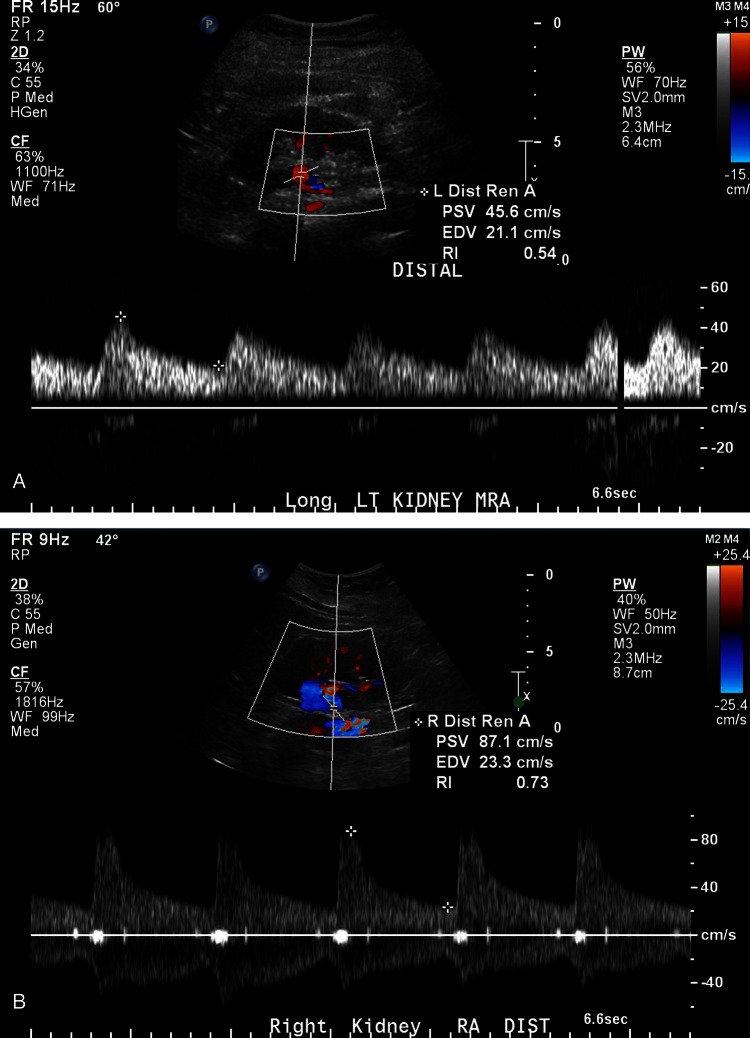

Figure 2.

(A) Doppler examinations of the distal main renal arteries revealed a markedly slowed upstroke on the left (A) with a very slow fall in flow after peak velocity (pulsus tardus et parvus) with a peak systolic flow of about 46 cm/s, end diastolic flow of 21 cm/s and a resistive index of 0.54. The left renal arterial Doppler study also showed a very turbulent flow pattern in the vessel, all consistent with proximal vascular stenosis. The right renal flow pattern in (B) showed a normal sharp upstroke, and rapid decay pattern, with a peak systolic flow of 87 cm/s, end diastolic flow of 23 cm/s and a resistive index of 0.73).